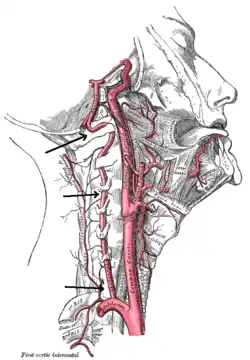

![]() | |

| Arteries of the neck, with arrows indicating the right vertebral artery | |

The vertebral arteries arise from the subclavian artery, and run through the transverse foramen of the upper six vertebrae of the neck. After exiting at the level of the first cervical vertebra, its course changes from vertical to horizontal, and then enters the skull through the foramen magnum. Inside the skull, the arteries merge to form the basilar artery, which joins the circle of Willis. In total, three quarters of the artery are outside the skull; it has a high mobility in this area due to rotational movement in the neck and is therefore vulnerable to trauma. Most dissections happen at the level of the first and second vertebrae. The vertebral artery supplies a number of vital structures in the posterior cranial fossa, such as the brainstem, the cerebellum and the occipital lobes. The brainstem harbors a number of vital functions (such as respiration) and controls the nerves of the face and neck. The cerebellum is part of the diffuse system that coordinates movement. Finally, the occipital lobes participate in the sense of vision.[1]